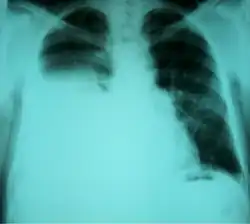

| Chest X-ray showing a hepatic hydrothorax in a person with cirrhosis | |